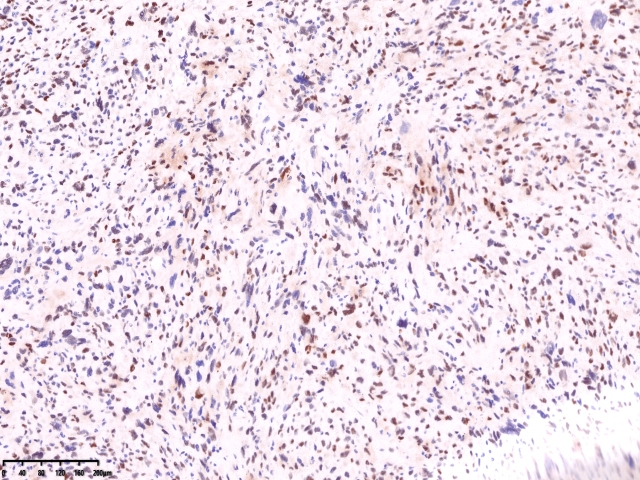

镜下可见肌间可见梭形瘤细胞,细胞核畸形,多核瘤巨细胞。坏死。

免疫组化

SMA

Caldesm部分+

CD10部分+

CD10

ki67

cd34

ER 部分+

PR-

Desmin-

会诊结果:子宫体间叶组织来源的肿瘤,形态学符合恶性。依据免疫组化结果,可排除肌源性肿瘤、胃肠间质瘤、子宫内膜间质肿 瘤、神经源性肿瘤、孤立性纤维性肿瘤等。 考虑可能为纤维肉瘤。